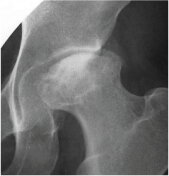

特発性大腿骨頭壊死症

股関節の中心である大腿骨頭が壊死(骨の細胞が死んでしまうこと)を起こしてつぶれ、強い痛みを生じる病気です。仕事盛りの壮年男性(お酒の飲みすぎと関係があると言われています)や、他の病気の治療(全身性ループスエリテマトーデス:SLEなど)のためのステロイドホルモン使用に関連して若い女性に発症することが多い病気です。壊死範囲が小さければ経過観察か骨頭の骨切り術をして壊死のないところで体重を支えるようにしますが、骨頭の破壊が進めば人工股関節が必要になります。